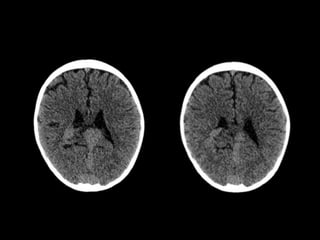

Hallazgos en TC

TC SIN CONTRASTE

o VPM ligeramente hiperdensa con el cerebro.

o Hidrocefalia.

o Hipodensidad y Ca++ de la sustancia blanca (SB)

subcortical ---> isquemia venosa crónica.

o Hemorragia intracraneal poco frecuente.

TC + C

o Realce vascular de arterias nutricias y VPM.

ATC

o Excelente definición angiográfíca de la MAVG